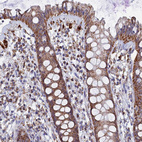

Immunohistochemical staining of human rectum shows strong granular cytoplasmic positivity in glandular cells.